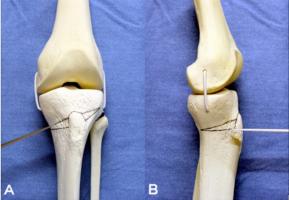

Actualité publiée le 28/01/2019MÉCANOBIOLOGIE : Pourquoi une blessure à l'articulation du genou mène à l'arthrose

Actualité publiée le 16/12/2018